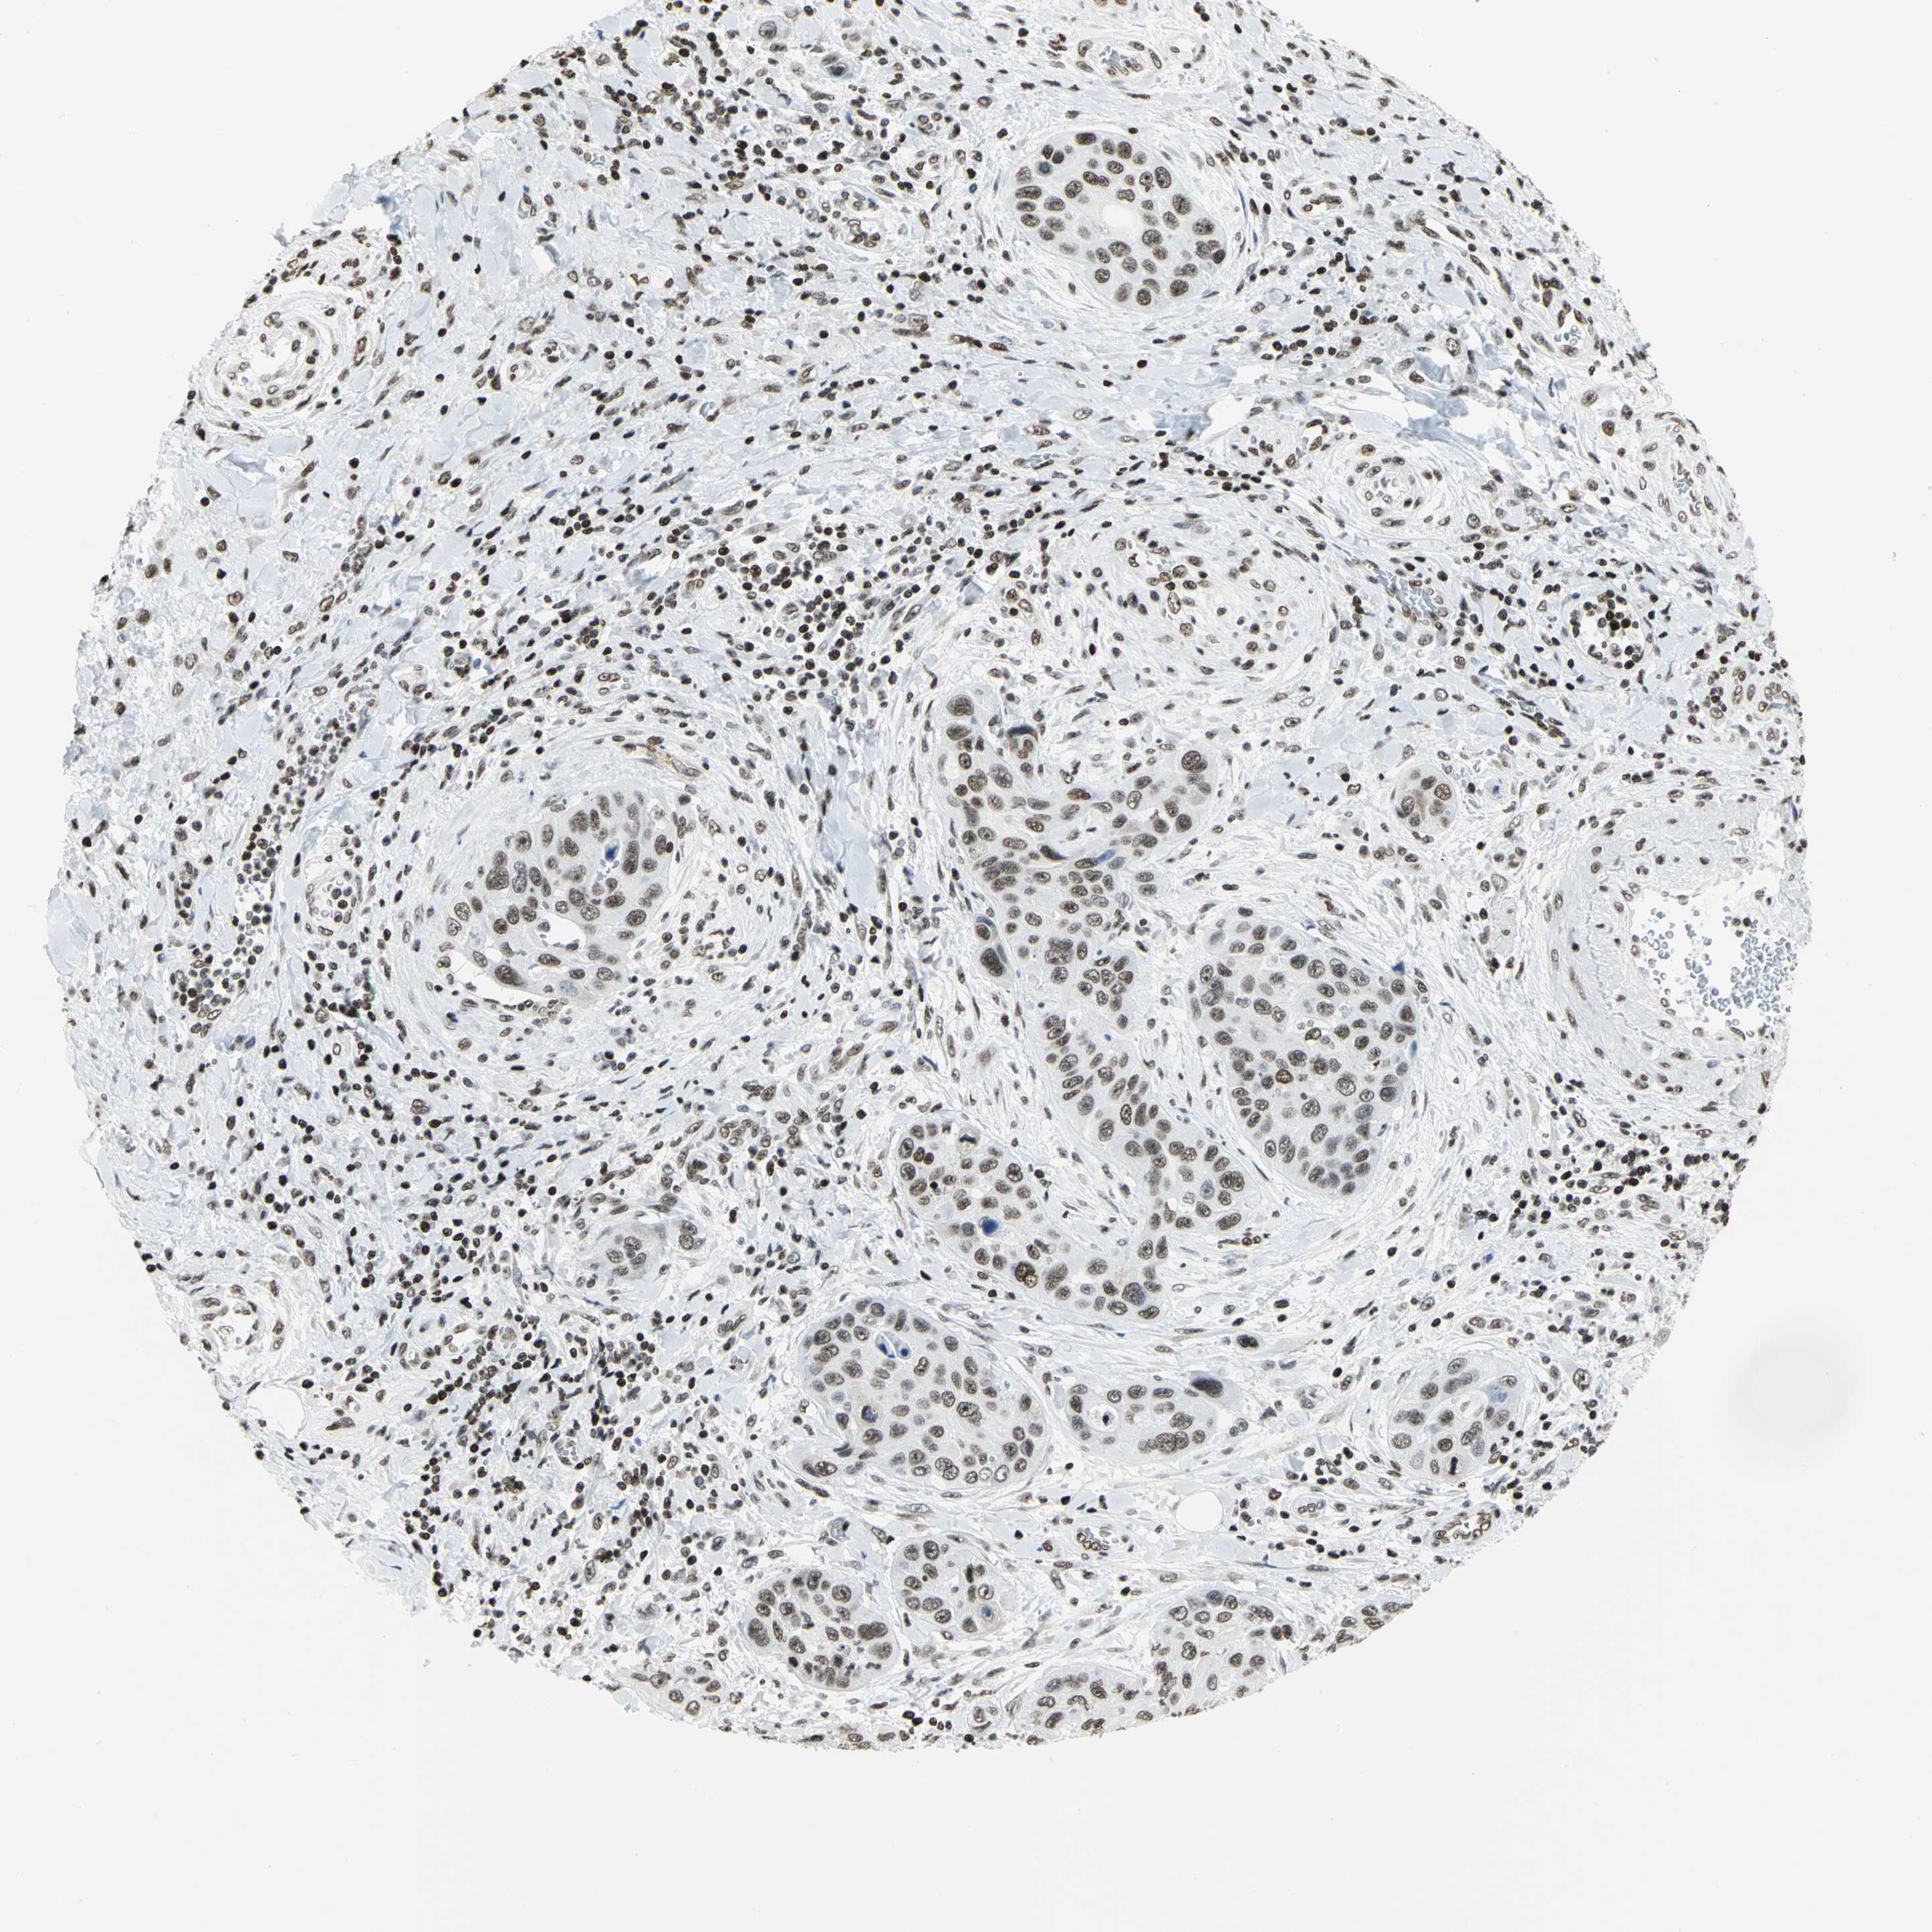

PANCREATIC CANCER - Protein expressioni

A mouse-over function shows sample information and annotation data. Click on an image to view it in a full screen mode. Samples can be filtered based on level of antibody staining by selecting one or several of the following categories: high, medium, low and not detected. The assay and annotation is described here.

Note that samples used for immunohistochemistry by the Human Protein Atlas do not correspond to samples in the TCGA dataset.

Antibody stainingi

Antibody staining in the annotated cell types in the current human tissue is reported as not detected, low, medium, or high, based on conventional immunohistochemistry profiling in selected tissues. This score is based on the combination of the staining intensity and fraction of stained cells.

Each image is clickable and will lead to virtual microscopy that enables deeper exploration of all samples and also displays staining intensity scores, fraction scores and subcellular localization as well as patient and tissue information for each sample.

Antibody HPA003506

Antibody CAB005873

Staining

High

Medium

Low

Not detected

Intensity

Strong

Moderate

Weak

Negative

Quantity

>75%

75%-25%

<25%

None

Location

Nuclear

Cytoplasmic/membranous

Cytoplasmic/membranous,nuclear

Adenocarcinoma, NOS

Adenocarcinoma, metastatic, NOS